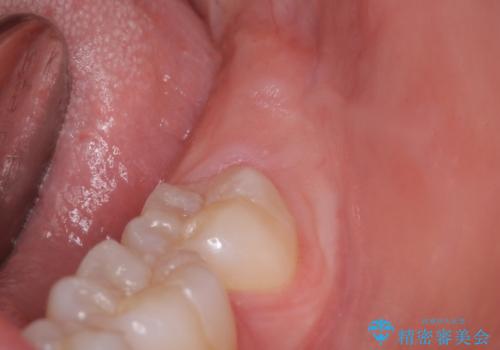

歯の高さを出すための親知らず抜歯と歯肉切除

担当医 岡田康成